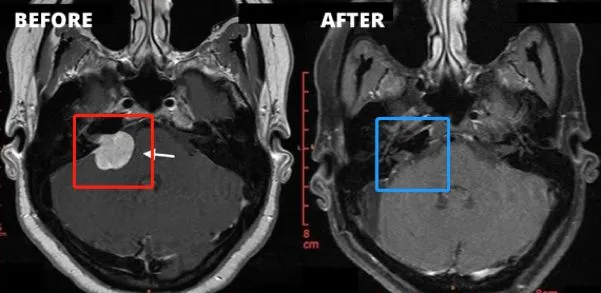

一位43岁男性患者在持续半年的右耳耳鸣后,逐渐出现听力下降、头昏头痛加重,以及面肌抽搐、面部麻木等症状。经检查确诊为听神经瘤,分级已达到Koos 3级、Samii T4a级,属于中大型肿瘤。面对这一结果,他陷入了两难:不手术,肿瘤持续生长,压迫神经的风险不断升级;选择手术,又担心术后出现面瘫或失聪。

经过充分评估,患者最终决定接受手术治疗。在术中神经电生理监测的全程护航与主刀医生丰富手术经验的支撑下,肿瘤被完全切除,术后既没有出现面瘫,听力功能也得到了有效保留。术后两周的面神经功能评估达到了House-Brackmann最高的1级标准,术后9个月随访显示,患者生活已完全恢复正常,未留下任何神经功能障碍。